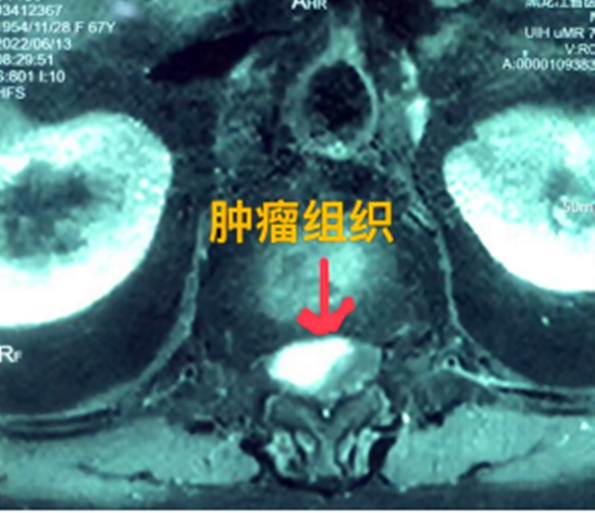

據(jù)省醫(yī)院神經(jīng)外一科陶宇醫(yī)生介紹,家住外地的張大娘最近總感覺雙下肢疼痛、無力,且排尿困難及便秘,伴有行走困難。時間長了,張大娘病情逐漸加重,劇烈的疼痛甚至讓她無法完整入睡。在當(dāng)?shù)蒯t(yī)院,張大娘按腰椎肩盤突出接受治療,但未見好轉(zhuǎn),隨后進行的胸椎MRI(核磁共振)檢查,結(jié)果不禁讓張大娘和家屬瞠目結(jié)舌,原來張大娘患的竟然是少見的脊髓腫瘤。

張大娘住進了黑龍江省醫(yī)院神經(jīng)外一科,該科孫國章主任醫(yī)師熱情地接待了張大娘,并邀請骨外一科專家共同為她進行了聯(lián)合會診。發(fā)現(xiàn)張大娘病情十分復(fù)雜棘手,脊髓腫瘤體積較大,充滿髓腔且神經(jīng)已經(jīng)完全受壓,需要手術(shù)來完整切除。同時還發(fā)現(xiàn)張大娘的胸腰部曾受過兩次外傷,伴有多處骨折,這對接下來的手術(shù)操作帶來一定影響。